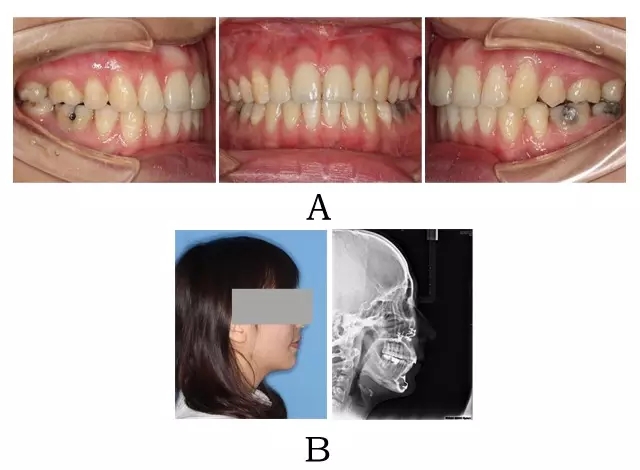

? 術式選擇:骨源性突面畸形的經(jīng)典術式是雙頜術式(上頜 LeFort I 型;下頜 BSSRO 或聯(lián)合頦成形術;或單獨頦成形術)(圖 2-3)。根據(jù)牙弓水平向不調(diào)的嚴重程度及下頜 Spee曲線的深凹程度,可附加分塊或根尖下截骨[7]。

對于上頜前突程度較輕、而下頜形態(tài)不良較嚴重的病例,可在正畸治療的基礎上獨立進行頦成形術。